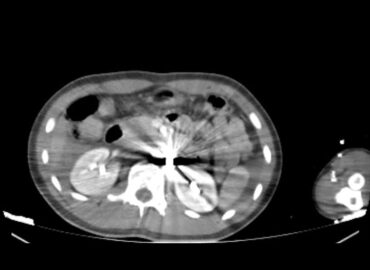

Masculino de 67 años. Dolor abdominal localizado en FII